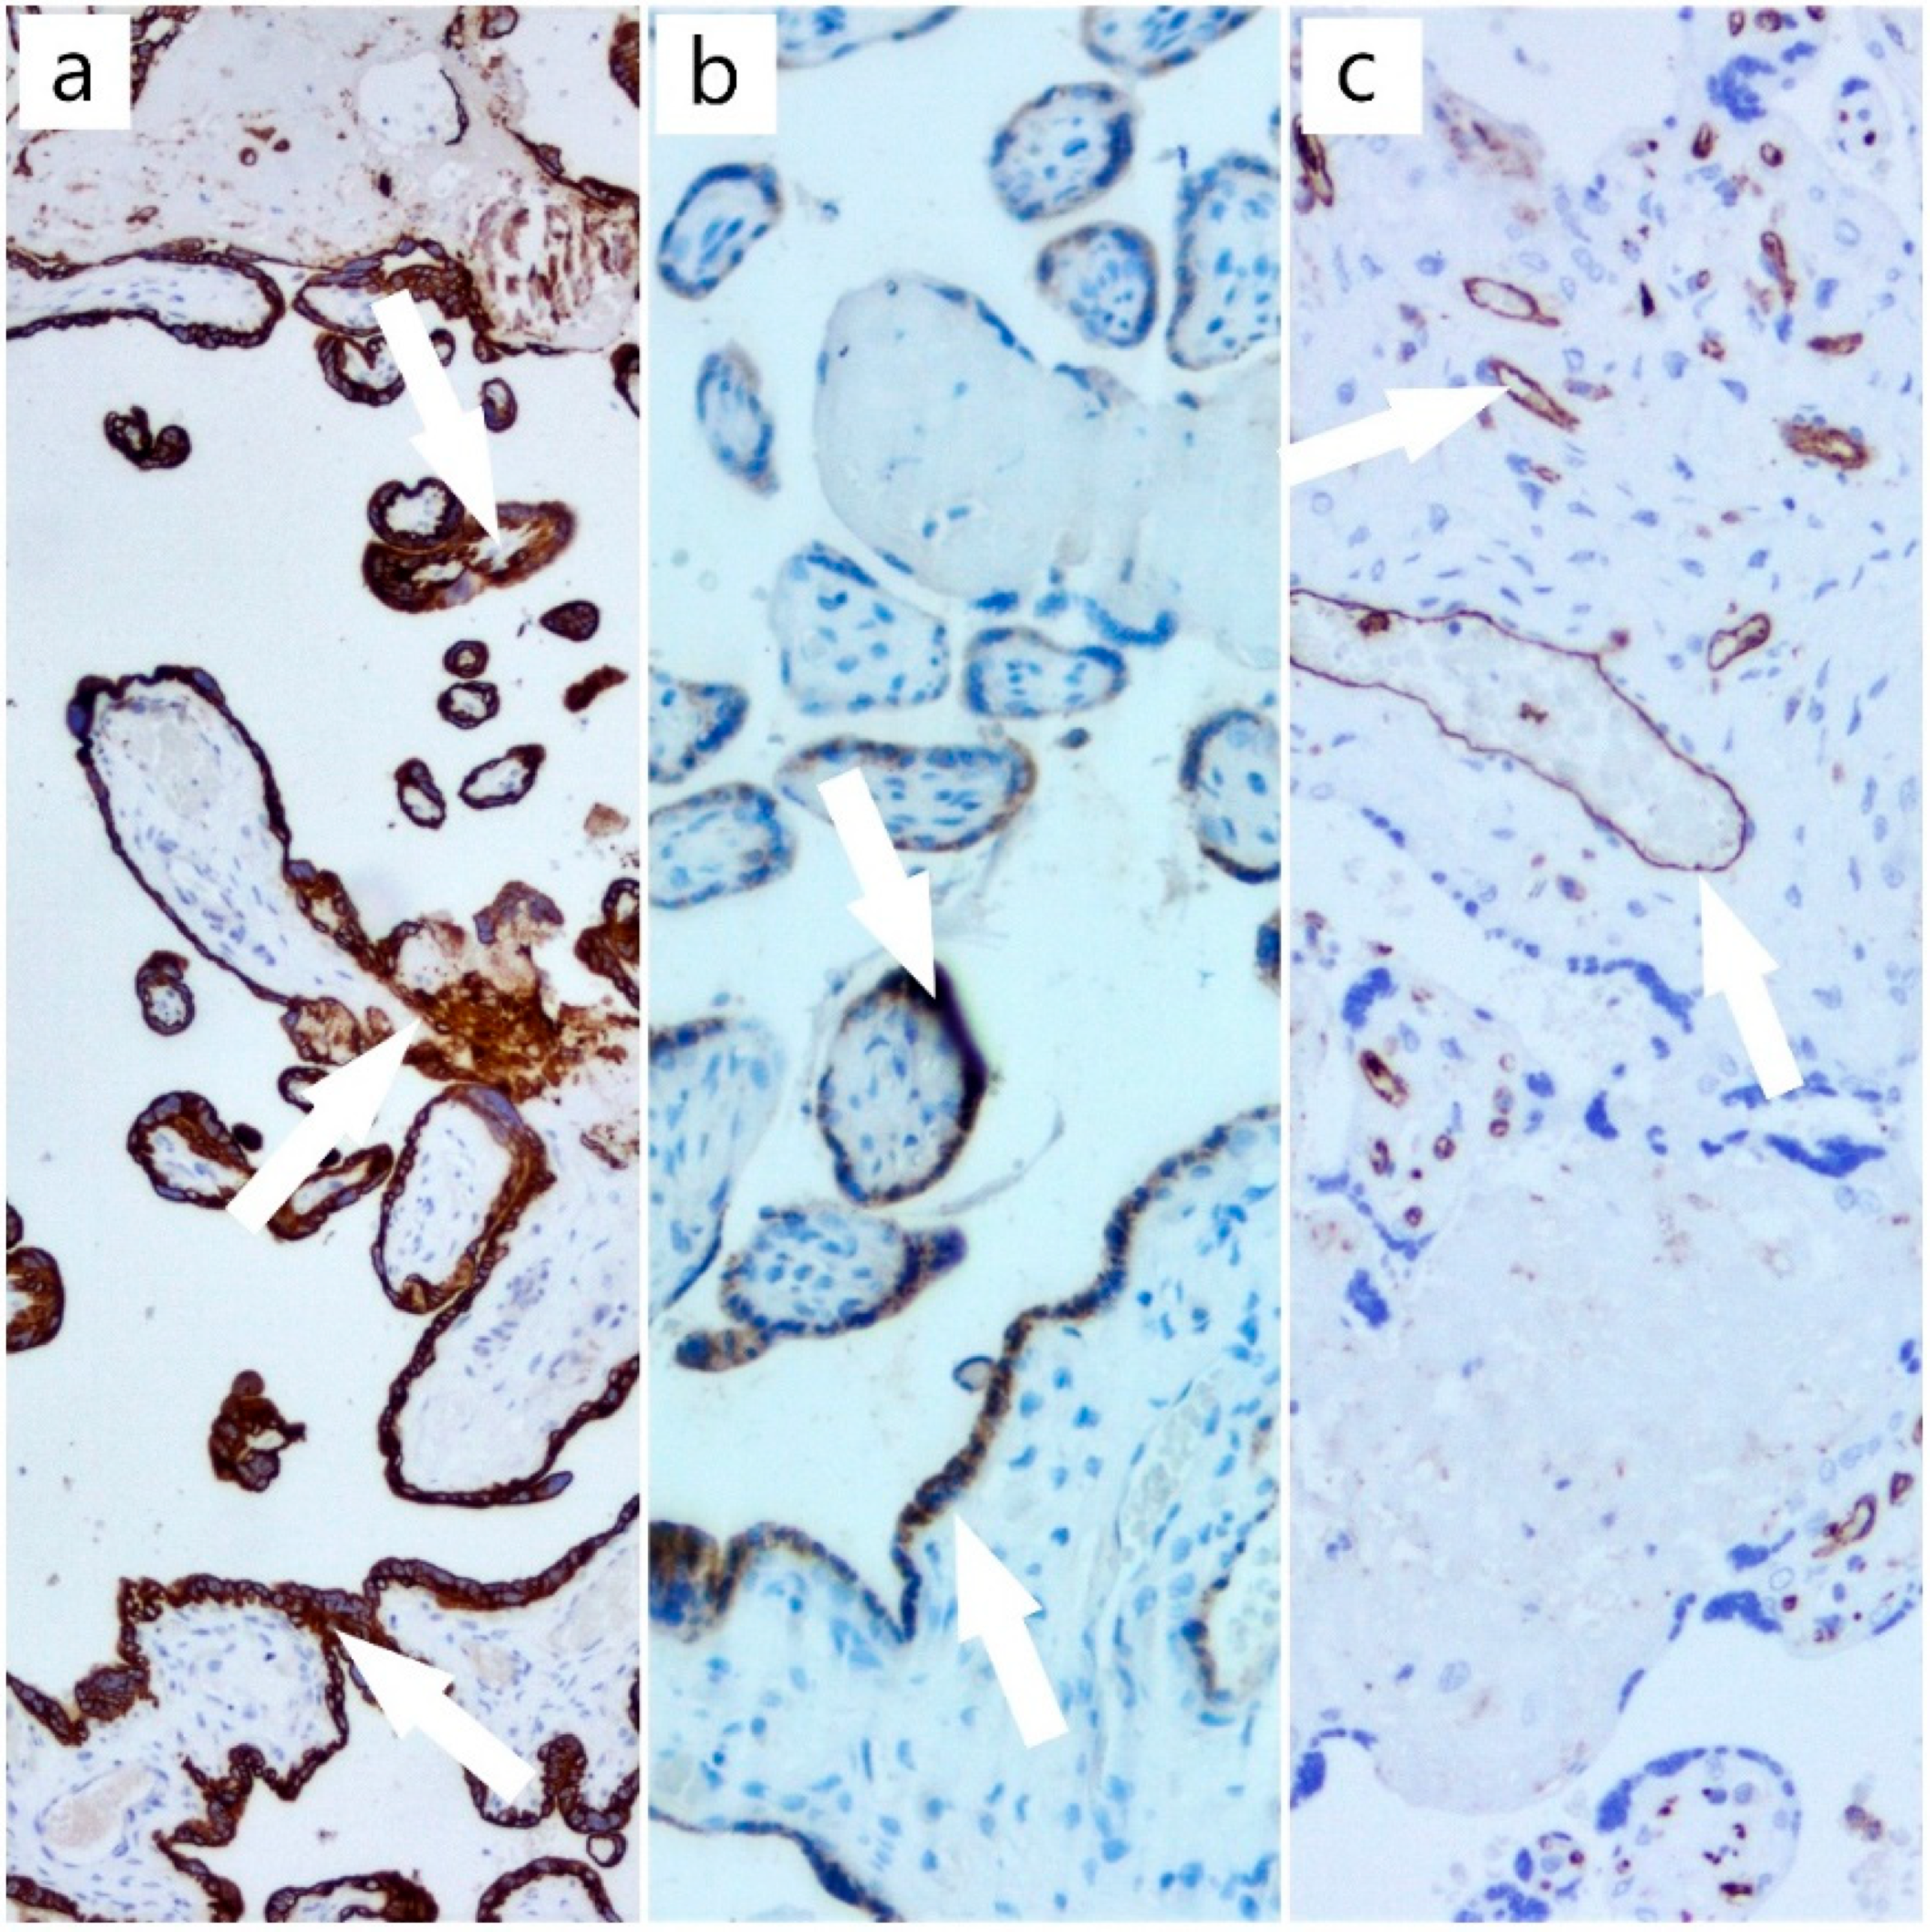

2. Case Report